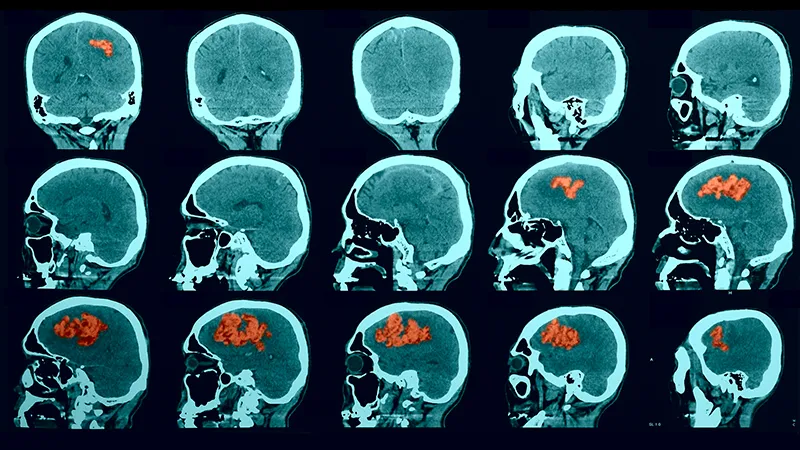

Understanding a Stroke

A stroke occurs when blood flow to the brain is blocked or a blood vessel within the brain bursts, resulting in damage to the affected brain tissue.